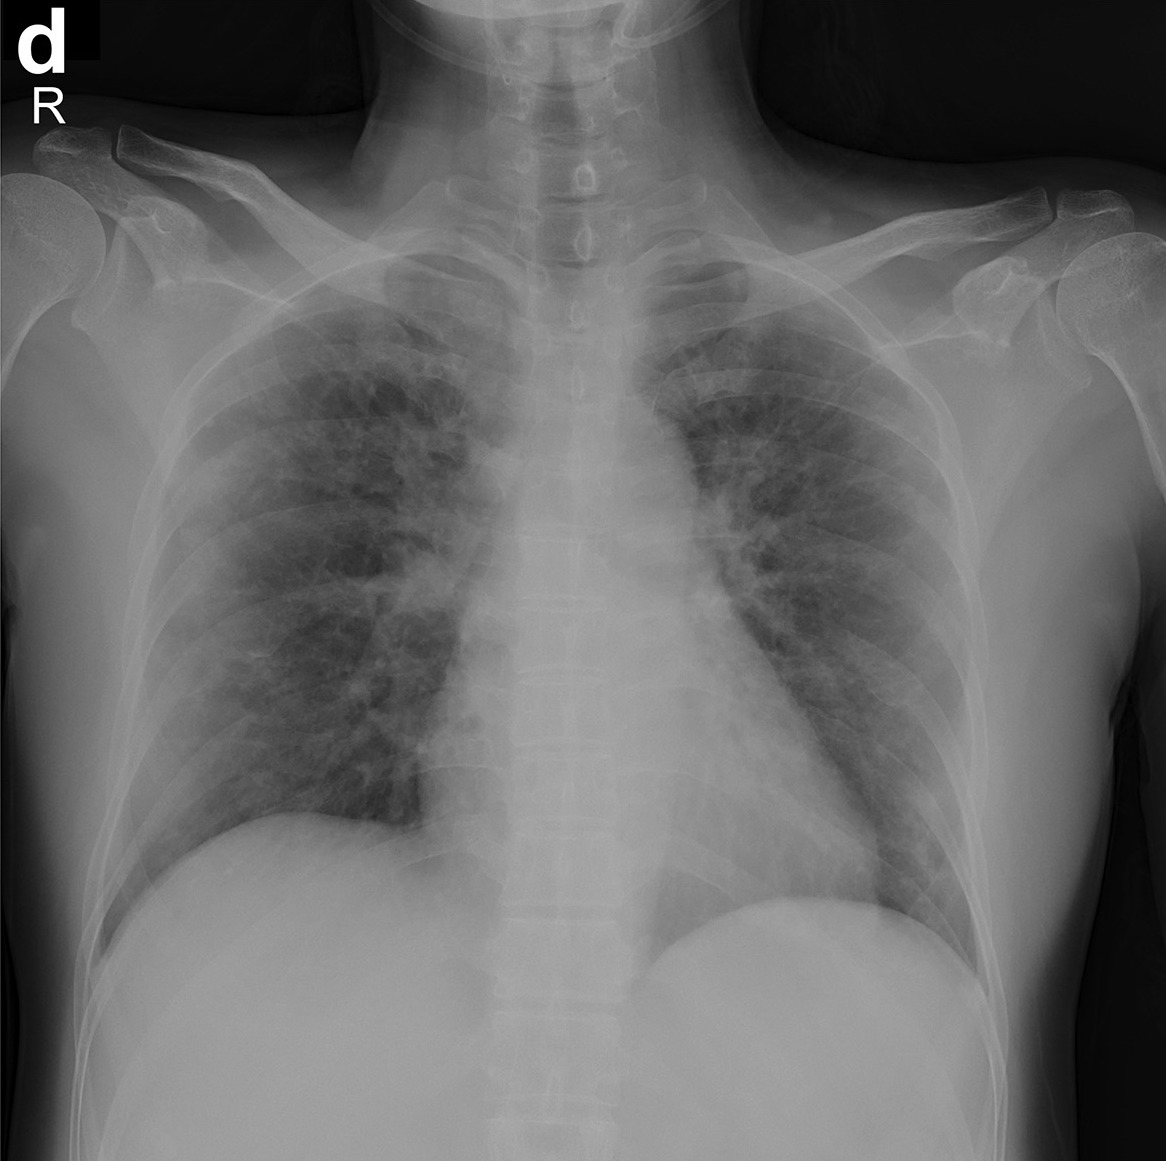

X-ray images can be obtained in every hospital. They are used by doctors for detecting COVID19. Let's automate it!

PyTorchLightning/lightning-Covid19 is a project using state-of-the-art libraries PyTorch and PyTorch-Lightning to classify the X-ray images for COVID-19.